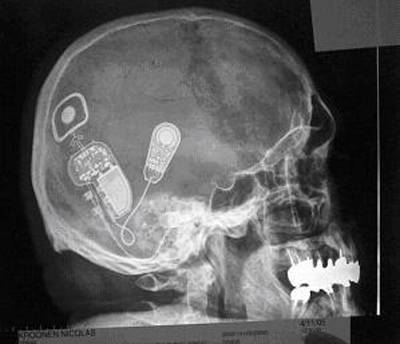

Une microcaméra, logée dans les verres d’une paire de lunettes de soleil, capte les images qui sont ensuite traitéespar un ordinateur porté à la ceinture. De là, des impulsions électriques sont envoyées, par l’intermédiaire d’un câble, vers un boîtier fixé sur le crâne où s’établit une connexion avec 68 électrodes (constituées de fil de platine de 1 millimètre de diamètre). Ces électrodes, fichées sur une plaque métallique, posée à la surface du cortex visuel, stimulent directement le cerveau.

Le dispositif permet au non-voyant de percevoir des points lumineux et de reconnaître certaines formes simples. Un Américain de soixante-deux ans, devenu aveugle à l’âge de trente-six ans, peut ainsi lire des caractères d’imprimerie de 15 centimètres à une distance de 1, 5 mètres (ce qui toutefois correspond à "une acuité visuelle très faible"). L’équipe américaine qui travaille sur ce projet pensait, à terme, perfectionner cette technique en implantant jusqu’à 512 électrodes, tout en intégrant les progrès de l’informatique (notamment en utilisant au mieux la technique d’analyse d’image connue sous le nom d’"extraction de contour").

Pourtant, lorsqu’il parvient à surmonter sa fatigue et sa souffrance, Ray contrôle un ordinateur par la force de sa pensée, grâce à un appareil électronique implanté dans son cerveau. Le système "capte ses signaux cérébraux et les retransmet à un processeur [qui les] convertit […] en commandes interprétables par un ordinateur".

Johnny Ray participe, depuis mars 1998, à une expérience exceptionnelle conduite par l’équipe du professeur de neurologie Philip Kennedy de l’université Emory d’Atlanta et Melody Moore, professeur d’informatique à l’Université d’État de Géorgie : à cette date, deux "électrodes neurotrophiques" ont été implantées dans le cortex moteur de Ray (là où se trouvent les cellules contrôlant divers groupes musculaires). Chaque électrode est constituée d’un cône de verre évidé d’environ 1,5 mm de longueur et de 0,1 à 0,4 mm de diamètre qui contient deux filaments en or capable d’enregistrer la présence d’un courant de faible impédance.

Les cônes sont recouverts de tissus nerveux extraits du genou du patient. Ce film “neurotrophique” (“qui reconstitue les tissus”) stimule la croissance cellulaire.

Dans les trois mois suivant l’implantation (effectuée dans la zone du cortex associée aux mouvements des mains), les dendrites des neurones qui entourent les électrodes se sont liées aux tissus qui se sont reconstitués dans le cône du verre, y créant "une sorte de mini-cerveau". Ainsi, lorsque Ray pense certains types de gestes, les électrodes captent les signaux émis par les neurones. Ces signaux sont transmis, via un amplificateur-transmetteur miniaturisé logé dans la boîte crânienne, à l’ordinateur qui les traduit en mouvements du curseur.

« Nous avons placé la souris de l’ordinateur dans le cerveau du malade », résume le neurochirurgien (Roy Bakay) qui a réalisé cet implant, sans trop pouvoir expliquer comment le patient parvient à contrôler les signaux émis par son cerveau.